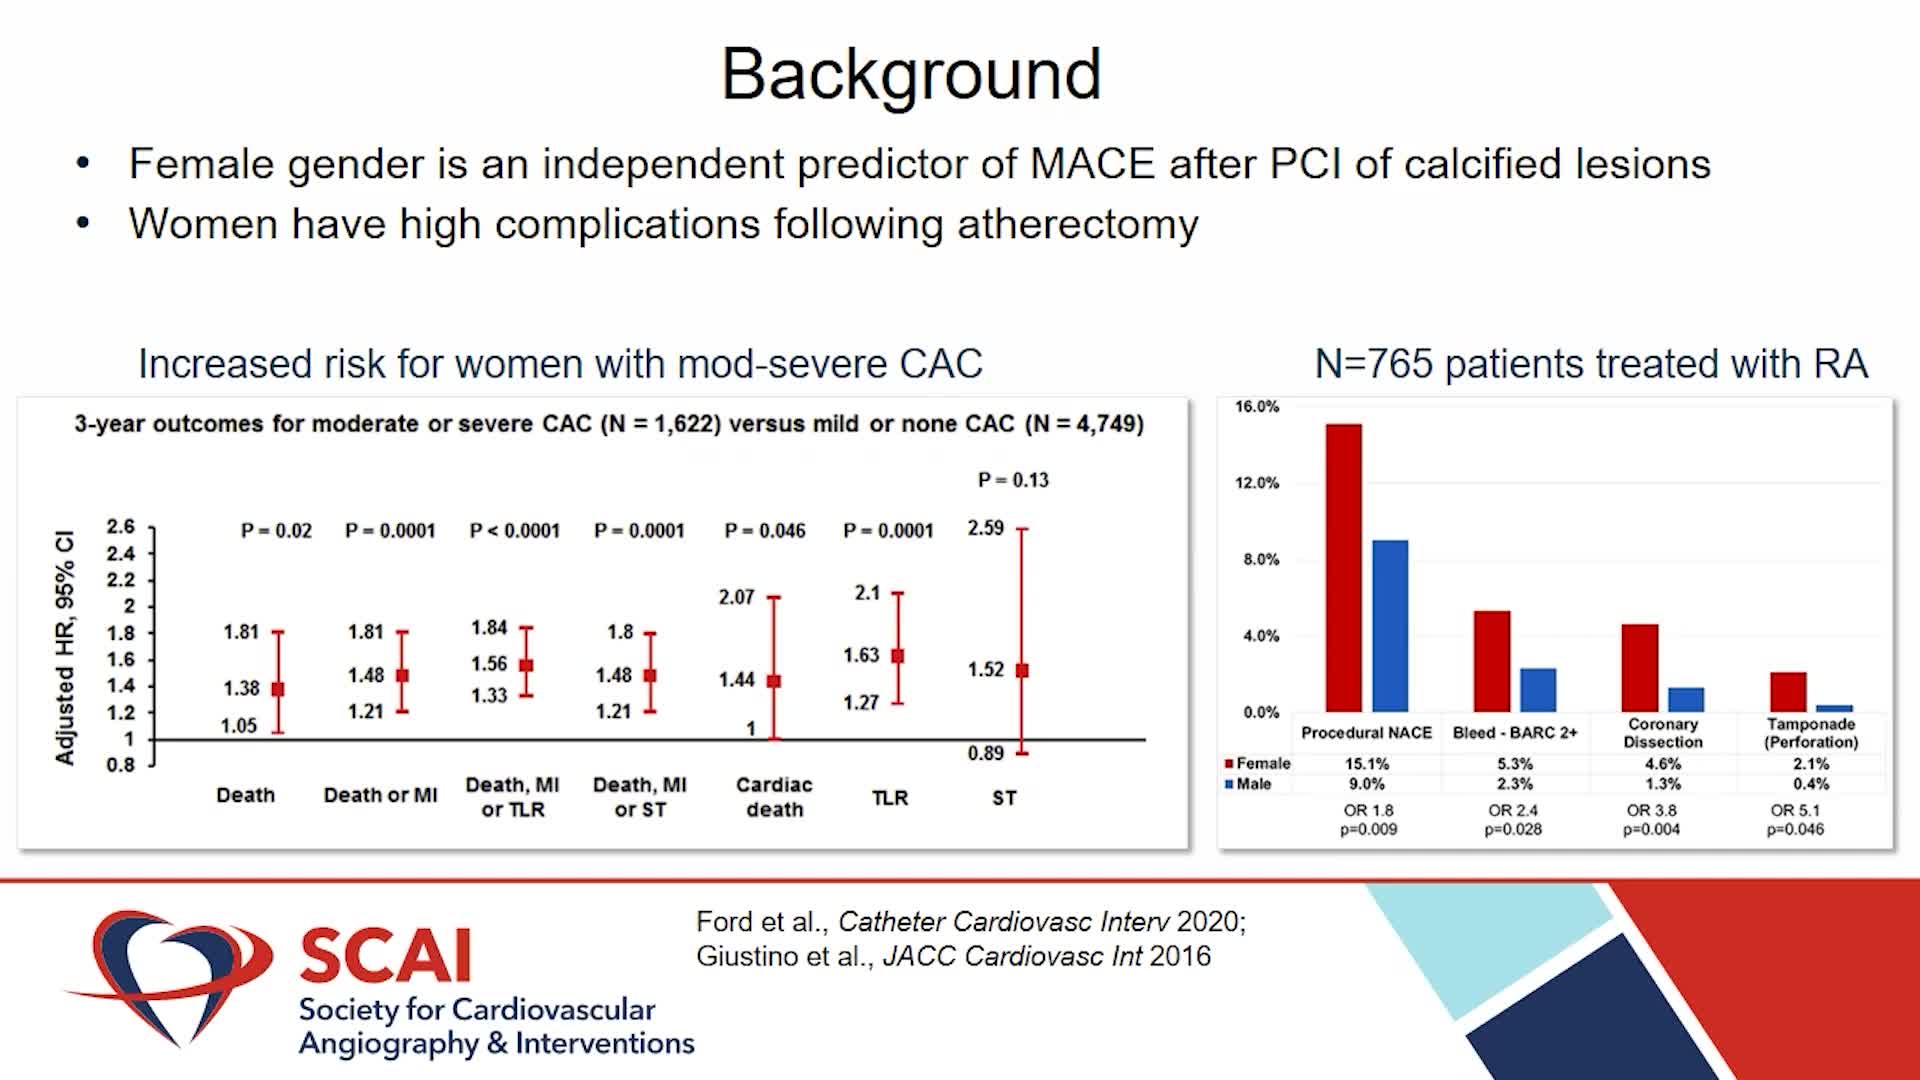

Real-World EU Experience: Coronary IVL Across Different Calcium Morphologies from TCT 2022